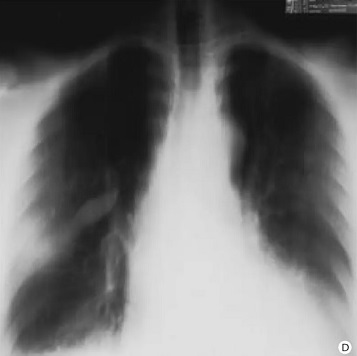

Aspect

radiologique d'une epanchement scissuraire du poumon

droit en coupe tomographie ( planigraphie ) de face

|

Mema cas en coupe

tomographie de profile . Aspect radiologique est

opacite em forme " fuseaux biconvex " à inferieure

du poumon droit |